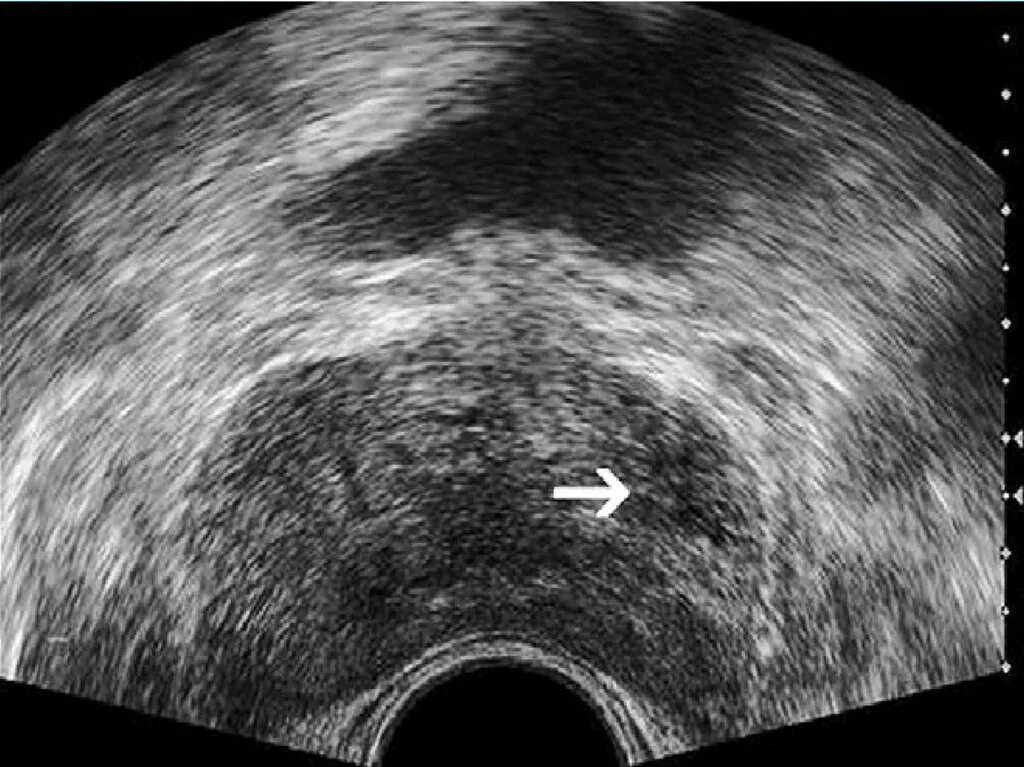

Диффузные предстательной железы